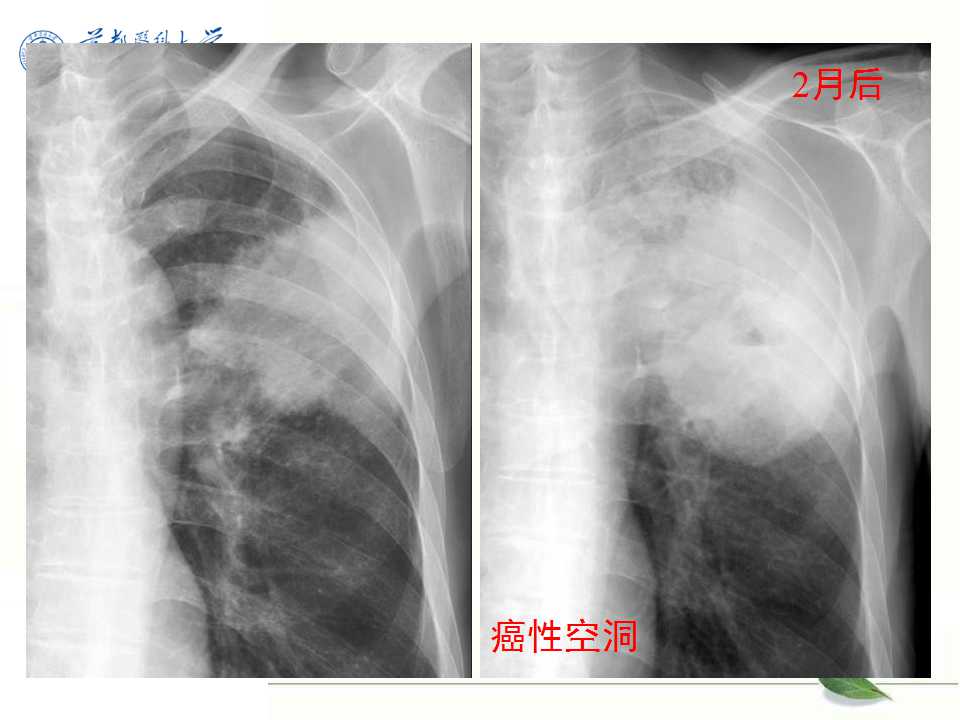

肺癌的影像学检查